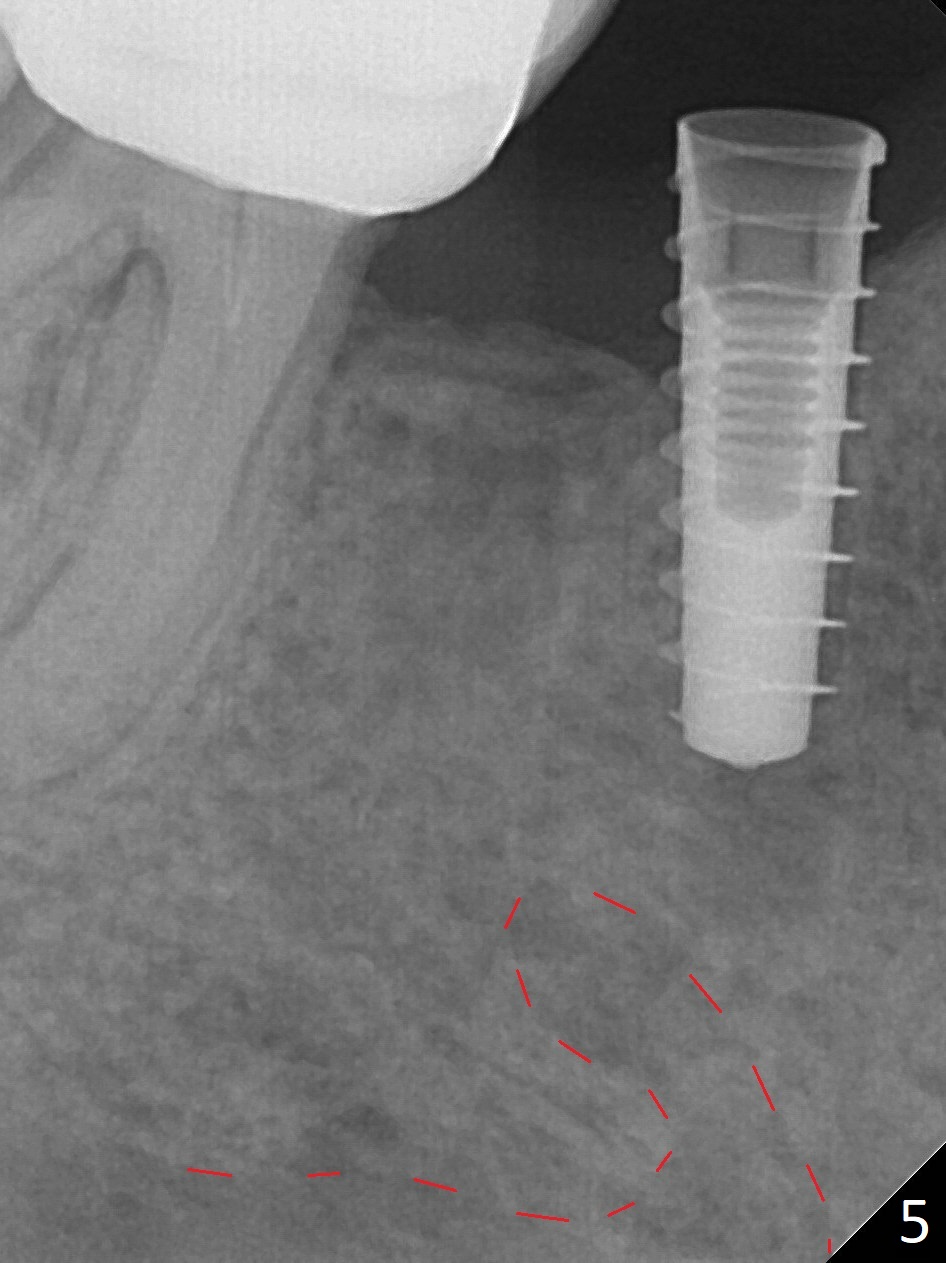

The patient returns for implant placement 11 months post extraction of #28 and 29. With flapless manner, initial osteotomy happens to drop into the original socket of #28 (Fig.4). After use of 3.3 mm Magic Drill (MD) and Final Drill for 15 mm, a 4x11 mm dummy implant is placed (Fig.5). It appears that the implant is long for the site (red dashed line: Mental Loop). However, a definitive implant (4x9 mm, IBS) has difficulty to reach its depth (Fig.6). After several rounds of untorque and retorque, the implant does not seat completely (Fig.7, implant driver disengagement) with autogenous bone placed distal (>). Retrospectively, a larger MD should have been used (3.8 mm) for complete seating in the dense bone. In fact she is post breast cancer treatment with 50% chance of relapse. The patient returns for follow up 1.5 months postop (Fig.8). The wound has healed. Impression is taken 5 months postop (Fig.9). When the crown is cemented, food impaction is an issue between the implant crown and crown at #30. Since the tooth #30 is mesially tilted with distal open margin and apical infection, the tooth will be extracted. Osteotomy is going to be initiated in the mesial slope of the mesial socket (Fig.9 red line). An implant will be placed more or less in the mesial socket (green box).